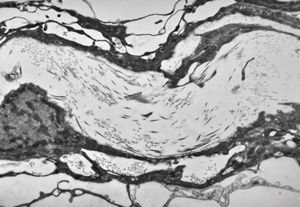

M, 63y. | cyst of choroid plexus - dystrophic calcification

M, 63y. | cyst of choroid plexus - dystrophic calcification

M, 63y. | cyst of choroid plexus - dystrophic calcification

M, 63y. | cyst of choroid plexus - dystrophic calcification

M, 63y. | cyst of choroid plexus - dystrophic calcification